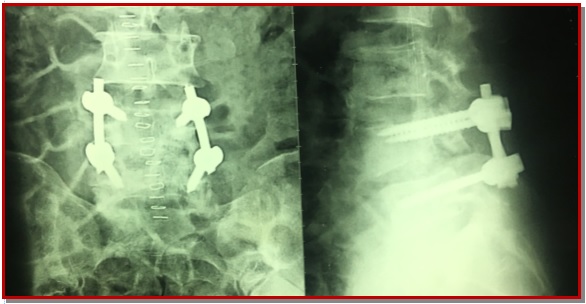

Posterior lumber interbody fusion with pedicle screw fixation for the management of spondylolisthesis: An analysis of 40 cases

Spondylolisthesis is forward slipping of upper vertebra in relations to its lower one, commonest is L4-L5. The ideal surgical treatment of spondylolisthesis is still controversial. Posterior lumber interbody fusion with pedicle fixation is one of treatment choices for the lumber spondylolisthesis. Forty patients who operated through posterior lumber interbody fusion and pedicle screw fixation by single surgeon was included from January 2012 to March 2015. Periodical follow-up was done both clinically and radiologically up to 6 months. Patient outcome was completed based on pain relief graphic rating scale and Oswestry disability index. In our series, the excellent outcome were 25 patients (62.5%), good were 12 patients (30%), and fair were 3 patients (7.5%). There were no poor outcome and no new neurological deficit. This study concludes that posterior lumber inter-body fusion with pedicle is an effective treatment for the lumber spondylolisthesis. It helps to maintain the biomechanics, associated with less complication and improve the quality of life of patient.